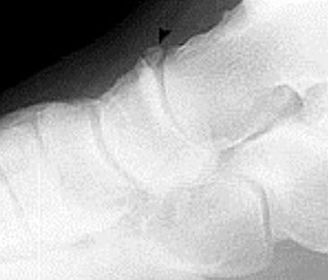

Describe what the arrows are showing | Torus fracture of the 1st met. "Buckling" of the proximal one third diaphysis is seen both medially and laterally. Common in paediatric patients |